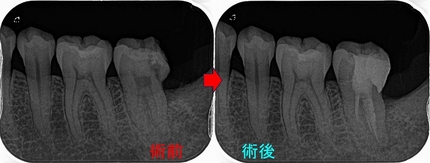

レントゲン

詰め物の下に大きな虫歯が見られ、応急的に詰めたのかレジンが歯の形になっていません。

電気歯髄診断を行うと数値は「7」、神経は多少の反応はあるが殆ど死んでいると判断できる数値

*EEデンタルの歯髄診断機「0~10」までで正常な神経だと1~2ぐらいで反応があります。

2026 EEdental TAY (2).jpg

樋状根でした。

*ML根は途中で石灰化をしており穿通できず、たぶん早い時期に治療をスタートしていれば穿通出来たかも!?